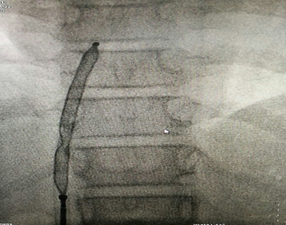

正在釋放的封堵器

在征得患者及家屬同意后,醫(yī)院心血管內(nèi)科手術(shù)團(tuán)隊(duì)在小章右側(cè)大腿根部做了局部皮膚麻醉,穿刺股靜脈成功后,經(jīng)血管插入一根幾毫米的導(dǎo)管,將封堵器送至缺損部位釋放。術(shù)后立即做心臟彩超及心電圖檢查,證實(shí)無殘余分流,無傳導(dǎo)阻滯等并發(fā)癥,手術(shù)成功。小章的先天性心臟病得到了“根治”,手術(shù)總共耗時(shí)約一個(gè)半小時(shí)。

封堵器釋放完畢